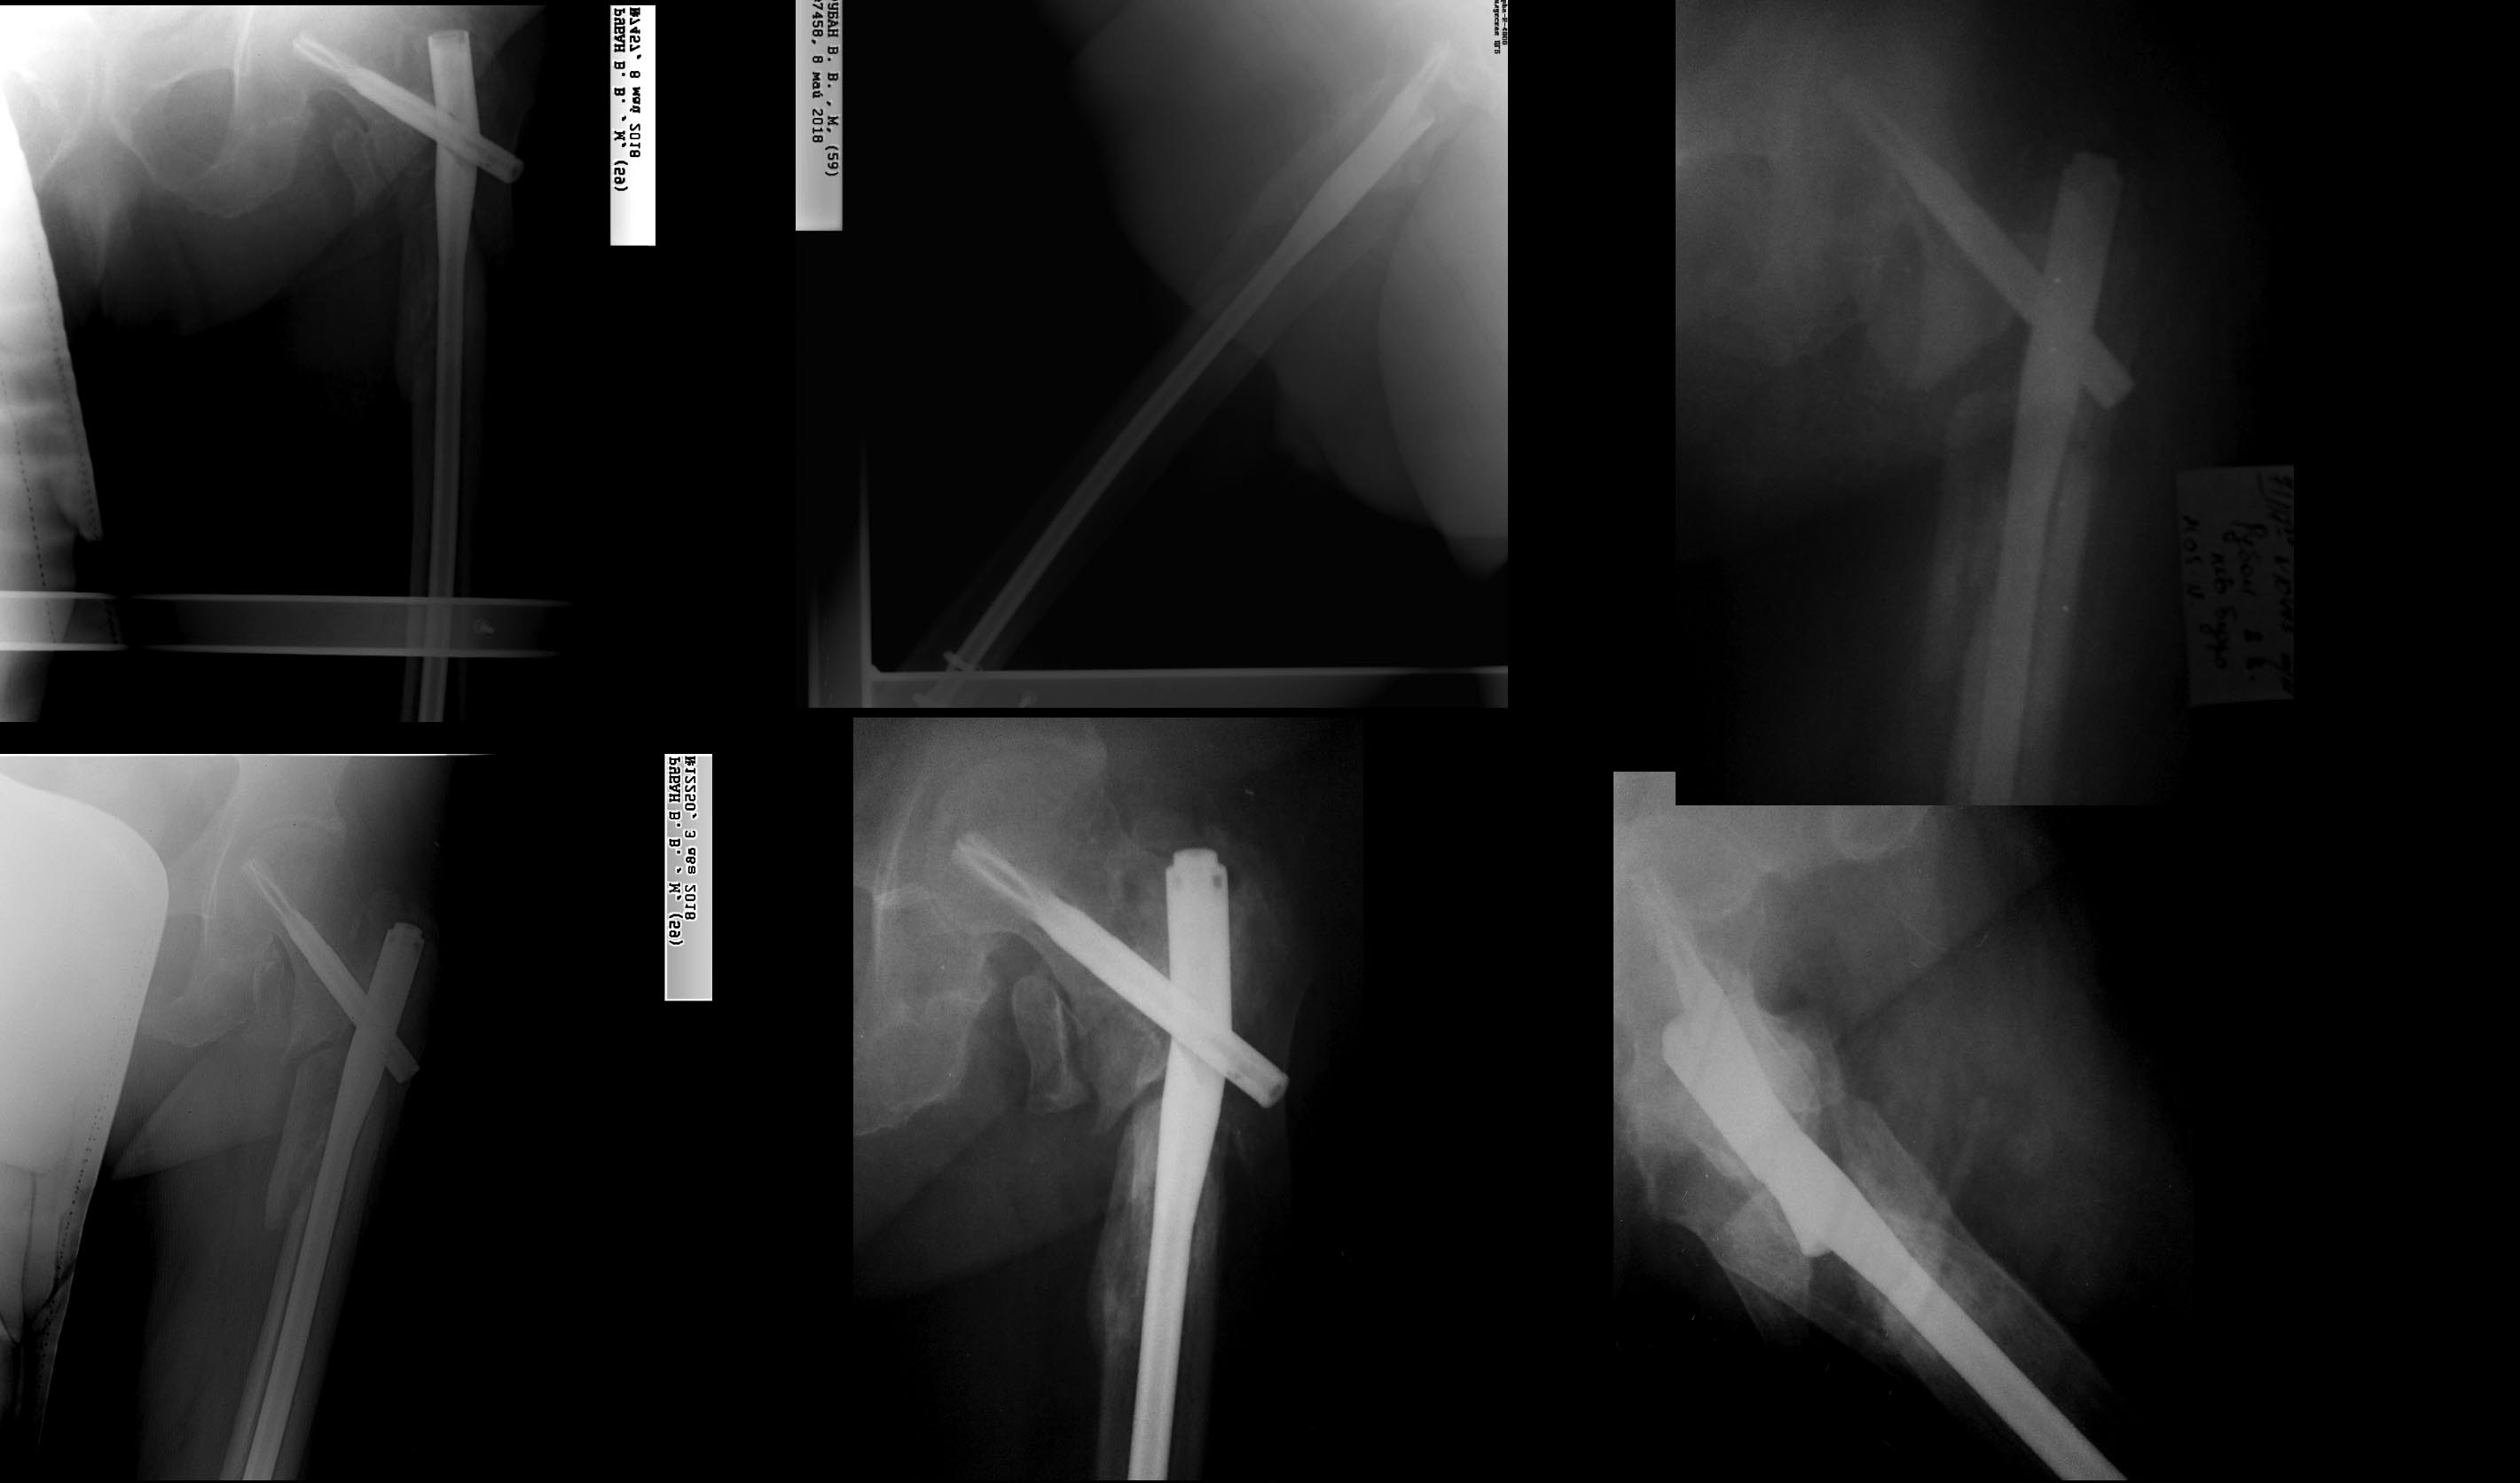

Уважаемые коллеги, подскажите пожалуйста дальнейшую тактику. Пациент 60 лет, вес 110 кг страдает сахарным диабетом. Оперирован(закрыто) в декабре 2017г.,в мае 2018г. перелом м. фиксатора-ресинтез. На контрольных рентгенограммах август 2018г-замедленная консолидация-предложен notching (по всей видимости нужно было сделать при ресинтезе), однако у пациента развилось ОНМК находился на реабилитации. На сегодняшний день имеется псевдоартроз с повторным переломом фиксатора, неврологически компенсирован. Возможно ли в данной ситуации заштифтовать короткой версией и notching, или же пластина с (без) костной пластикой? С Ув. Накоренок Илья

Похоже, в первый раз заштифтовали с переудлинением, и не динамизировали вовремя. Notching был не нужен, основание шеечного винта не фиксировало латеральную стенку периферического отломка. Как раз в этом отношении все было хорошо, винт был погружен под кортекс.

Сейчас IMHO стоило бы сделать реостеосинте с вальгизацией, может быть, сделать чрескожную межвертельную остеотомию (это как раз будет вместо костной пластики). И на столе хорошо сколотить отломки, и запереть гвоздь динамически.

При ресинтезе основание шеечного винта фиксировало латеральную стенку периферического отломка,гвоздь был заперт динамически и телескопирование произошло до определенного уровня.(Rо-3 августа). Возможно,в данном случае, стоило бы больше расточить овальное отверстие.